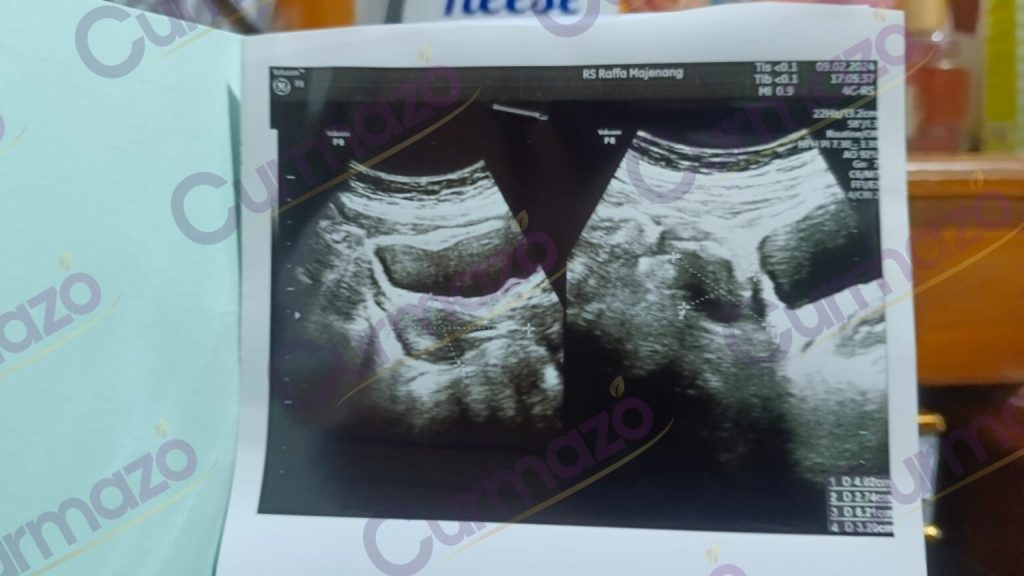

Awalnya, perut dan pinggang saya sakit sekali dan haid saya tidak teratur. Saya takut jika terjadi sesuatu di tubuh saya, sehingga saya melakukan pemeriksaan dan hasilnya ada kista sebesar 6.21 cm.

Saya bingung harus mencoba pengobatan apa karena saya tidak mau dioperasi, akhirnya sampai pada tanggal 15 Februari 2024 saat saya sedang melihat facebook, ada pengobatan herbal yang bisa menyembuhkan kista tanpa operasi. Saya tertarik dan langsung berkonsultasi. Mereka menyarankan saya untuk mengkonsumsi herbal Curmazo & K-Muricata.

22 Februari 2024, saya mulai mengkonsumsi herbalnya sesuai dengan dosis yang diberikan dan juga dipandu untuk mengubah pola makan saya.

1 bulan konsumsi herbal, siklus haid saya mulai normal. Tapi pinggang masih sering terasa sakit.

2 bulan konsumsi herbal, saya merasa kondisi saya semakin membaik sehingga saya melakukan pemeriksaan USG. Kata dokter kista saya sudah mengecil menjadi 3 cm.

Alhamdulillah saya bersyukur sekali menemukan herbal yang bagus seperti ini. Saya akan terus mengkonsumsi herbal ini sampai kista saya hilang total dan juga untuk menjaga kesehatan saya.